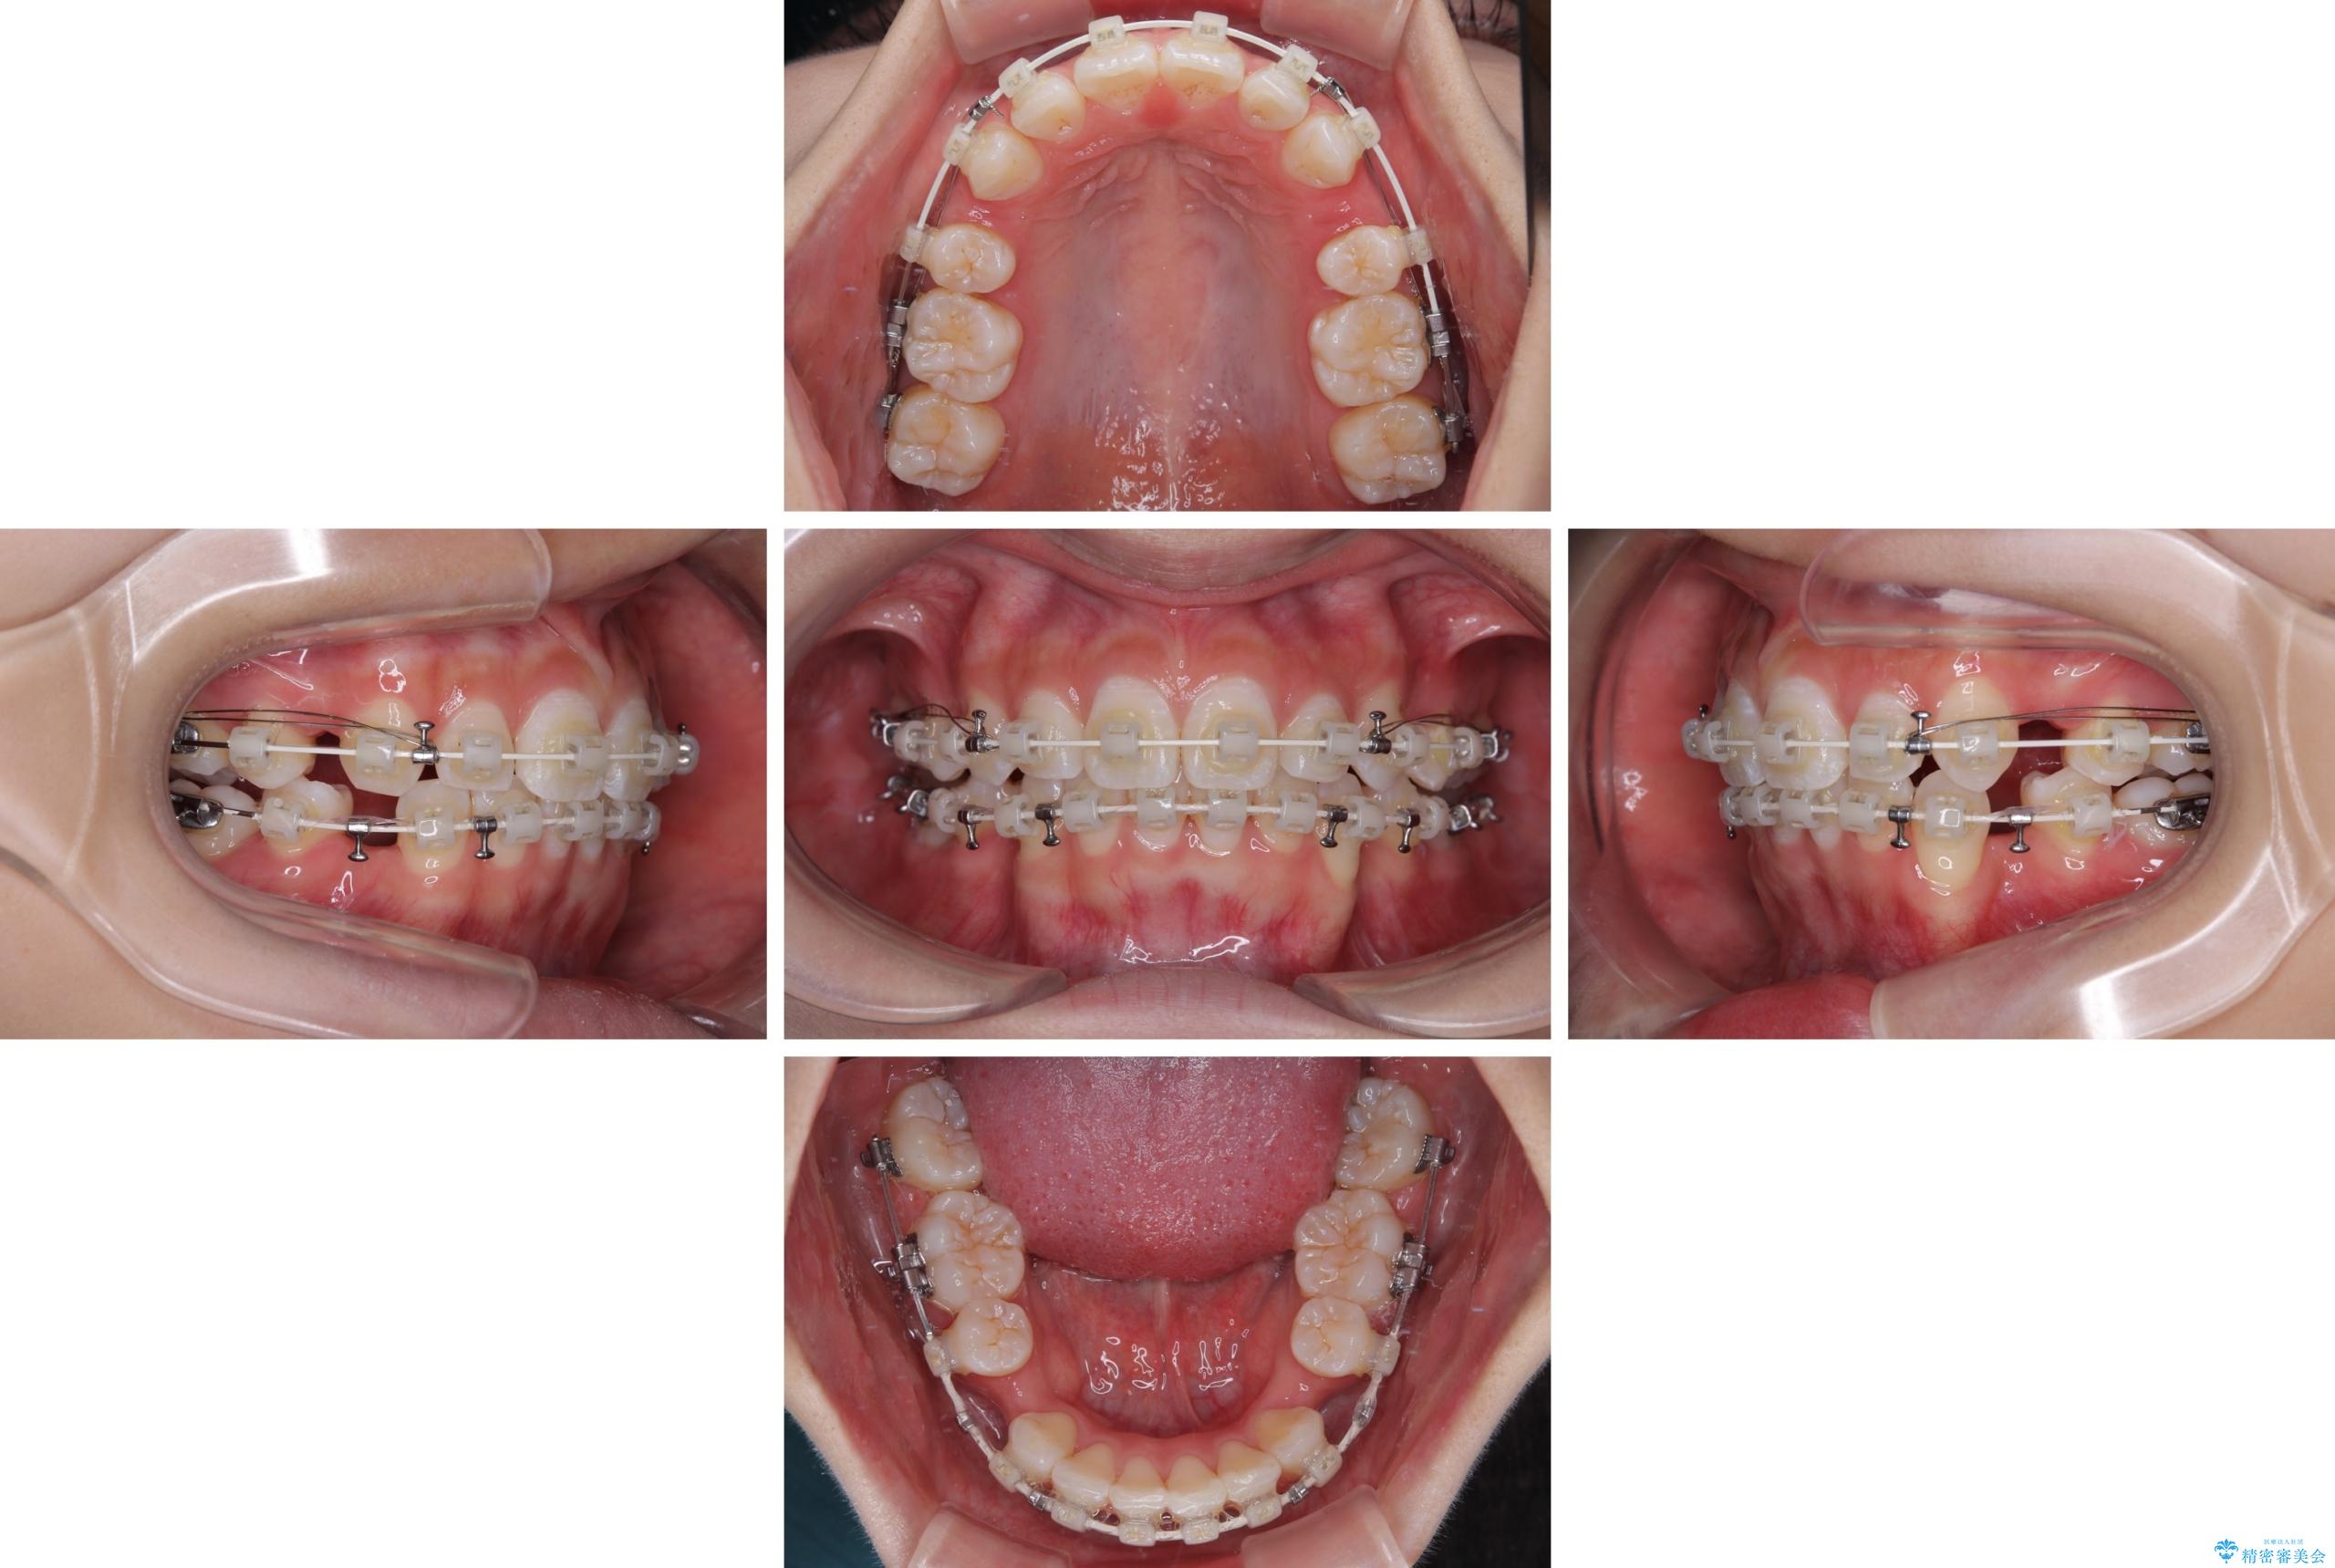

- 矯正装置

- 審美装置

- 口を閉じたときに飛び出してしまう上顎前歯を気にして来院された患者様です。

下顎はデコボコが気になっていたため、上下左右第一小臼歯4本を抜去して、ワイヤー装置にて口元の突出感を改善するよう矯正治療を行うこととしました。

下唇に前歯が当たって跡が残ってしまう状態でしたが、スッキリとした口元に仕上げることができました。